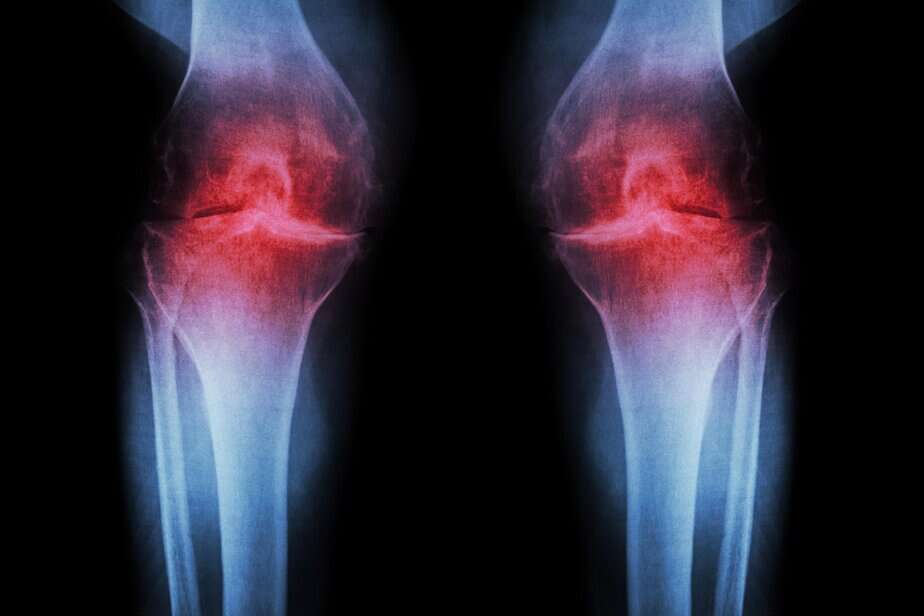

Anti-Aging Injection Regrows Knee Cartilage and Prevents Arthritis